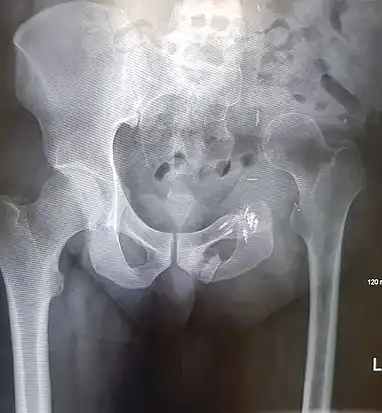

An x-ray of a limb-sparing hemipelvectomy on the left side of a male pelvis taken one month after surgery.